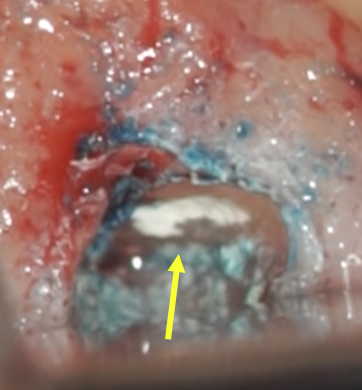

• 治療時画像、黄色矢印はMB1の根管、緑矢印部がMB2があるであろう場所ですが、根管らしきものは石灰化のため見えません。

• もう少し歯根を切断すると、イスムス(黄色矢印)が出てきました。感染源です。

• MB1ごとイスムスを超音波の器具で取り除いているところ。

• 未処置の感染部分の除去後、お薬(バイオセラミックパテ)を充填したところ。